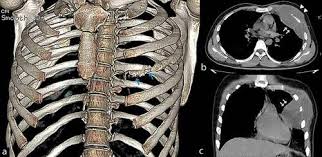

How Is Rib Osteomyelitis Diagnosed?

Diagnosis involves a combination of clinical evaluation and diagnostic tests:

- Medical History and Physical Examination: Assessing symptoms and risk factors.

- Imaging Studies: MRI is particularly useful for detecting bone and soft tissue involvement.

- Laboratory Tests: Blood tests to identify signs of infection.

- Biopsy or Aspiration: Obtaining a sample from the affected area to identify the causative organism.